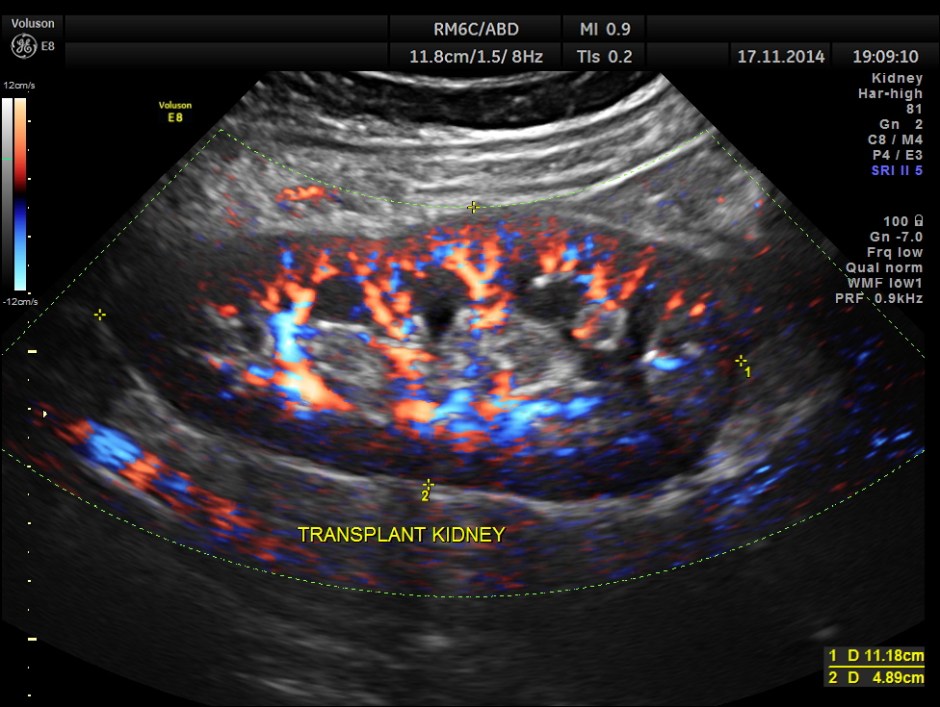

The following pictures show the transplanted kidney in the Right Iliac Fossa, with normal architecture, good Power Doppler flow and normal Spectral Doppler values.